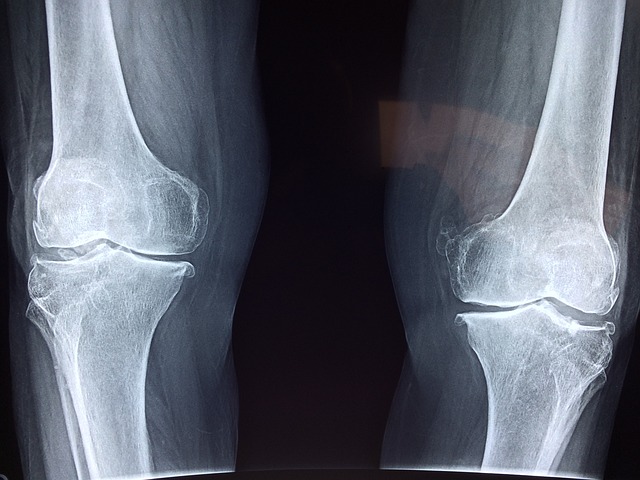

Лицата со оваа состојба може да почнат да забележуваат проблеми со зглобовите во 30-тите години, а првите симптоми може да бидат болка во долниот дел од грбот, колената, колковите и во рамената. Со текот на времето, може да има потреба за операција за замена на колкот, но не се очекувани поголеми симптоми.